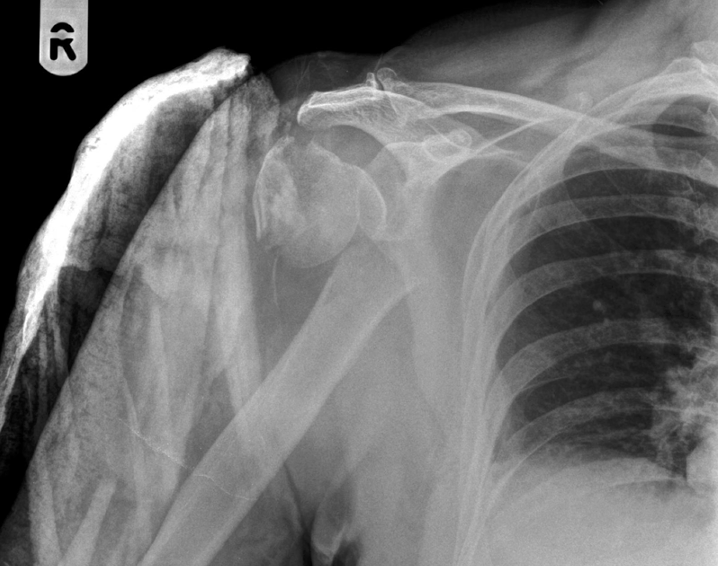

Q

in the shown radiograph

1- what type of fracture

2- site of fracture

3- any dislocation

A

Comminuted fracture of proximal humeral metaphysis with shortening and dislocation of the shoulder joint